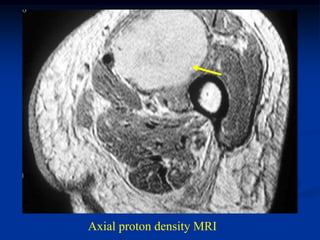

Case #276

64 year male with spindle cell lipoma proximal forearm

Sagittal T-1 MRI

Axial T-1 MRI

Axial proton density MRI